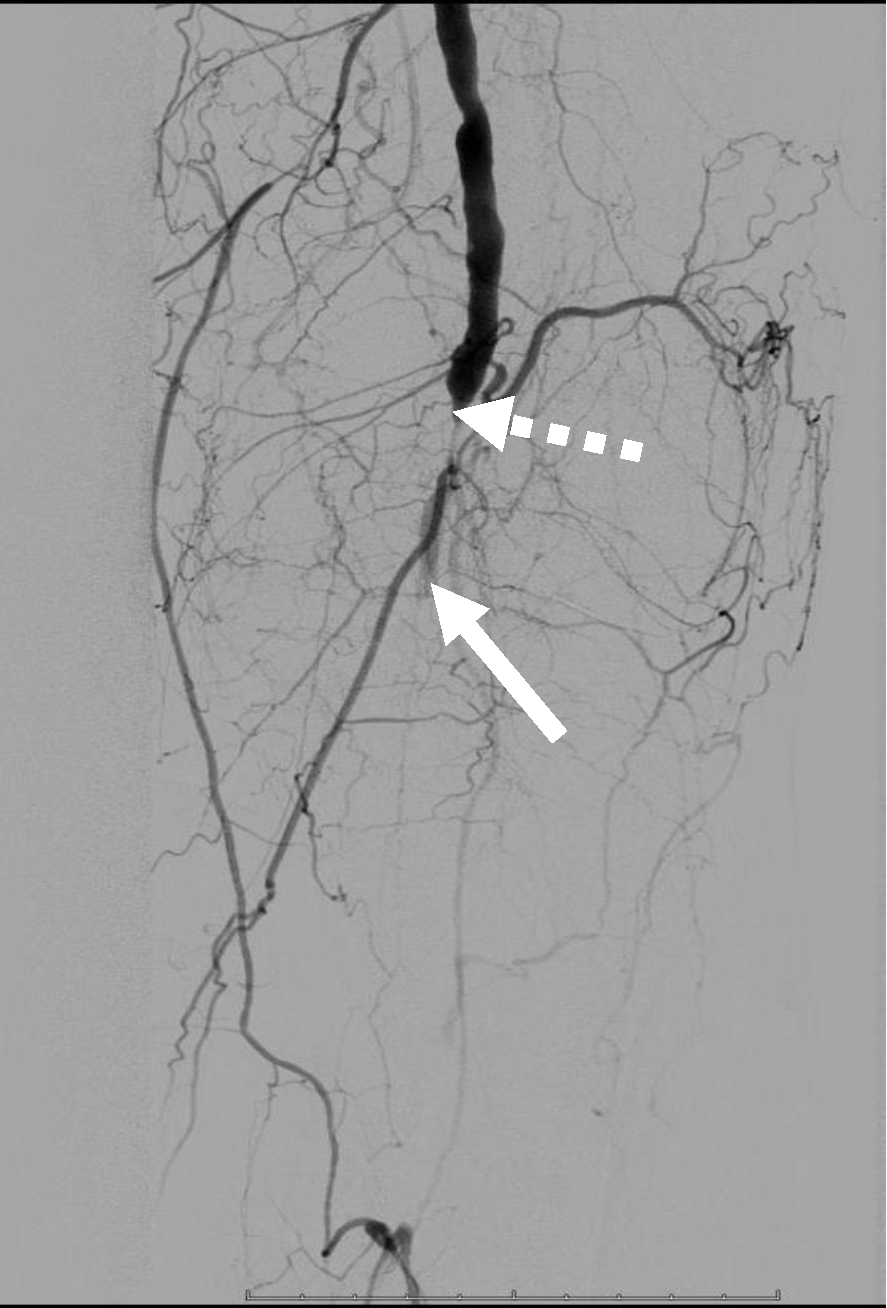

Операция. Транслюминальная баллонная ангиопластика (ТЛБАП) подколенной артерии, тибиоперонеального ствола слева. Под м/а выполнена пункция левой бедренной артерии, установлен интродьюсер 6 Fr. Выполнена селективная ангиграфия артерий левой нижней конечности при которой выявлена субокклюзия подколенной артерии и окклюзия тибиоперонеального ствола (рис. 1). Выполнена ТЛБАП в зоне субокклюзии баллоном 5,0 × 40 мм, давление 8 атм. В области тибиоперонеального ствола ТДБАП баллоном 3,0 мм × 100 мм, давление 10 атм. Получен хороший антеградный кровоток в подколенной, заднебольшеберцовой и малоберцовой артериях (рис. 2). Передняя большеберцовая артерия окклюзирована.

Рис. 1. Ангиограмма больной М. до ангиопластики. Стеноз подколенной артерии (прерывистая стрелка). Окклюзия артерий голени (сплошная стрелка)